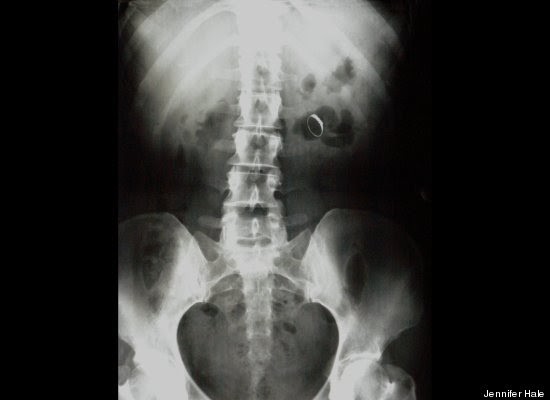

"Stack Up!" es una muy divertida colección de 100 imágenes de rayos X que muestra cuerpos extraños ingeridos o insertados en el cuerpo humano, tanto por accidente o de forma voluntaria, aunque se haga difícil imaginar el motivo de algunas de tales inserciones.

Los autores del libro -dos psiquiatras y un médico de sala de emergencias- aseguran -sin mucha originalidad pero con conocimiento de causa, que la imaginación humana no tiene límites. Esta afirmación es aplicable tanto a la calidad y variedad de objetos tragados o incorporados al cuerpo, como a los motivos o excusas utilizados para justificar la presencia de dichos objetos.

"Hay gente que hace cosas realmente imprudentes, y luego trata de racionalizarlas", advierten los autores en la solapa del libro, destacando precisamente la imaginación humana para "dar con usos imprevistos para objetos de la vida cotidiana".